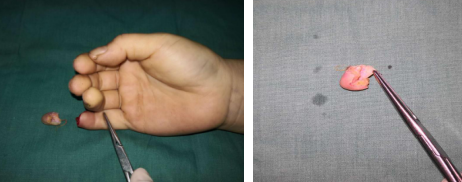

“这能接上吗?”家住徐州泉山区的马阿姨,从市区一三甲医院推荐过来,抱着试试看的心态,来到了仁慈医院手外科。这位马阿姨是被小孙子关卧室门时,不慎挤伤--指尖部的完全离断,如果是用皮瓣来修复创面,拆东墙补西墙,无疑对供区带来损伤,而且耐磨程度也不够,最好的办法就是给她接上,让它”破镜重圆”,可是这是谈何容易呀!马阿姨糖尿病、高血压多年,身体基本条件也不是太好,但是患者抱着最后一丝希望来到我院,不能让她失望而去呀,经过唐洪伟小组反复讨论,确定手术方案—清创再植!

术中吻合血管情况,血管管径仅有0.3mm

唐洪伟医生说:这个手术难度比较大,令人头疼。主要是血管太细,不容易找到,找到以后,需要非常高的显微外科技术,可能很多人一看这种情况,就直接放弃再植手术了。还有就是患者高血压、糖尿病多年,血管有不同程度的硬化,弹性差,影响术后成活,同时也面临着万一不成话,还需要二次手术等心理压力,不过看着病人,对我信任的眼神和殷切的希望,我还是决定立即行再植手术。现在患者手术成功,功能正常,手指活动非常灵活,非常满意。